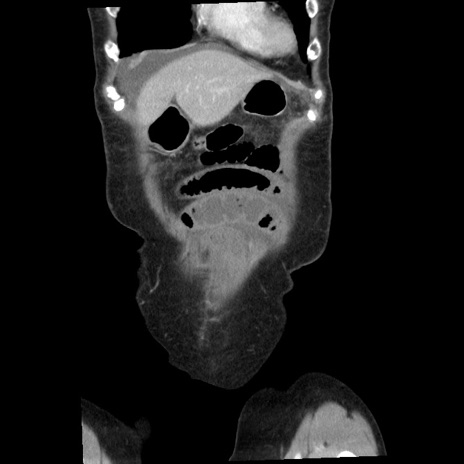

症例1(冠状断像)

【症例】80歳代女性

【主訴】腹痛

【現病歴】8時間前から腹痛あり来院。

【既往歴】糖尿病、脂質異常症、子宮体癌にて子宮全摘術

【身体所見】意識清明・会話良好だが腹痛で苦悶様、全腹部にわたって反跳痛と圧痛あり

【データ】WBC 13600、CRP 0.14、LDH 224、CK 90